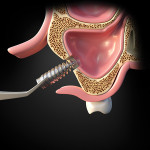

In 2013, the patient presented with the chief complaint of a loose restoration and pain in the maxillary left posterior area. When an orthopantomogram (OPG) was taken, the implant and permanent abutment at the site of tooth No. 14 was found to be displaced into the maxillary sinus (Figure 1). The patient was informed of the problem and advised of the potential complications if the implant/abutment was not removed. He then consented verbally and in writing to its removal after a discussion with the clinician of the risks and possible complications of the measures needed to be taken to perform this procedure.

Using the OPG of the sinus, the clinician examined the site of displacement and detected the implant/abutment and determined it to be apically located. The patient was asked to move his head in different directions. Two successive OPG images were then taken to determine that the implant/abutment was not attached to the sinus wall or located close to the ostium; this was apparent because the implant/abutment position changed when the patient moved his head in various directions (Figure 2). It was then decided to retrieve the implant/abutment from the sinus by using a lateral window approach.

After local anesthesia was obtained using lidocaine 2% with 1:100,000 epinephrine (2% Xylocaine®, Dentsply Sirona, dentsplysirona.com), an osteotomy was made through the lateral widow with a #8 round bur. A large amount of granulomatous tissue was found around the implant/abutment accompanied by bad odor and pus. A suction was used to aspirate the chronic inflammatory cells and fluid. Thorough irrigation was performed with sterile saline solution. A fiber-optic light was then used to locate the implant, and a bone rongeur was used to retrieve the implant from the sinus.

Techniques to retrieve an implant from the sinus are described in the literature and include a Caldwell-Luc procedure in which access to the sinus is obtained through the canine fossa. A second method achieves access through the alveolar crest to retrieve the displaced implant (Figure 6 and Figure 7).24 A third technique uses a lateral window that allows enhanced vision and improved accessibility compared to the other techniques(Figure 8 through Figure 10).25,26 Another method that is often attempted is to access the sinus by using an endoscope, which can be done either intraorally or intranasally; this technique, however, can be challenging, especially if the implant is detached from the sinus floor.27

In the present case, a lateral window was used, because it allowed better access than a crestal approach to locate and retrieve the implant/abutment. Although a crestal approach is less invasive, it would have required widening the original osteotomy used to place the implant and may have caused damage to the sinus because the implant was coronal and distal to this area. Also, removing the implant through the small crestal opening would have been difficult. Such an approach could have caused several additional complications when removing the implant, including damage to the sinus and remaining implants. The prosthesis had loosened from the supporting implants and was removed prior to the lateral window surgery. Although removal of the prosthesis in this case was therefore easy, this scenario emphasizes the value of a screw-retained versus a cement-retained prosthesis to allow retrievability. The lateral window approach can be more invasive than the crestal approach; however, it enables improved access and visibility for removal of the displaced implant from the sinus. Once access was achieved using the lateral wall approach, sinus debridement with the use of a suction was performed. After sinus lavage, a fiber optic light was employed to easily locate the implant/abutment.